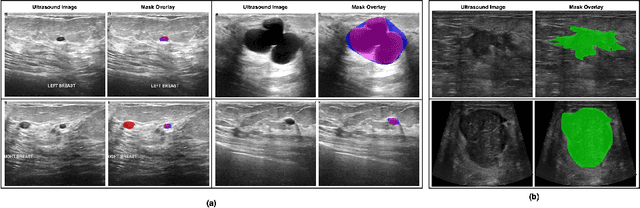

Abstract:Automated segmentation of BUS images is important for precise lesion delineation and tumor characterization, but is challenged by inherent artifacts and dataset inconsistencies. In this work, we evaluate the use of a modified Residual Encoder U-Net for breast ultrasound segmentation, with a focus on uncertainty quantification. We identify and correct for data duplication in the BUSI dataset, and use a deduplicated subset for more reliable estimates of generalization performance. Epistemic uncertainty is quantified using Monte Carlo dropout, deep ensembles, and their combination. Models are benchmarked on both in-distribution and out-of-distribution datasets to demonstrate how they generalize to unseen cross-domain data. Our approach achieves state-of-the-art segmentation accuracy on the Breast-Lesion-USG dataset with in-distribution validation, and provides calibrated uncertainty estimates that effectively signal regions of low model confidence. Performance declines and increased uncertainty observed in out-of-distribution evaluation highlight the persistent challenge of domain shift in medical imaging, and the importance of integrated uncertainty modeling for trustworthy clinical deployment. \footnote{Code available at: https://github.com/toufiqmusah/nn-uncertainty.git}